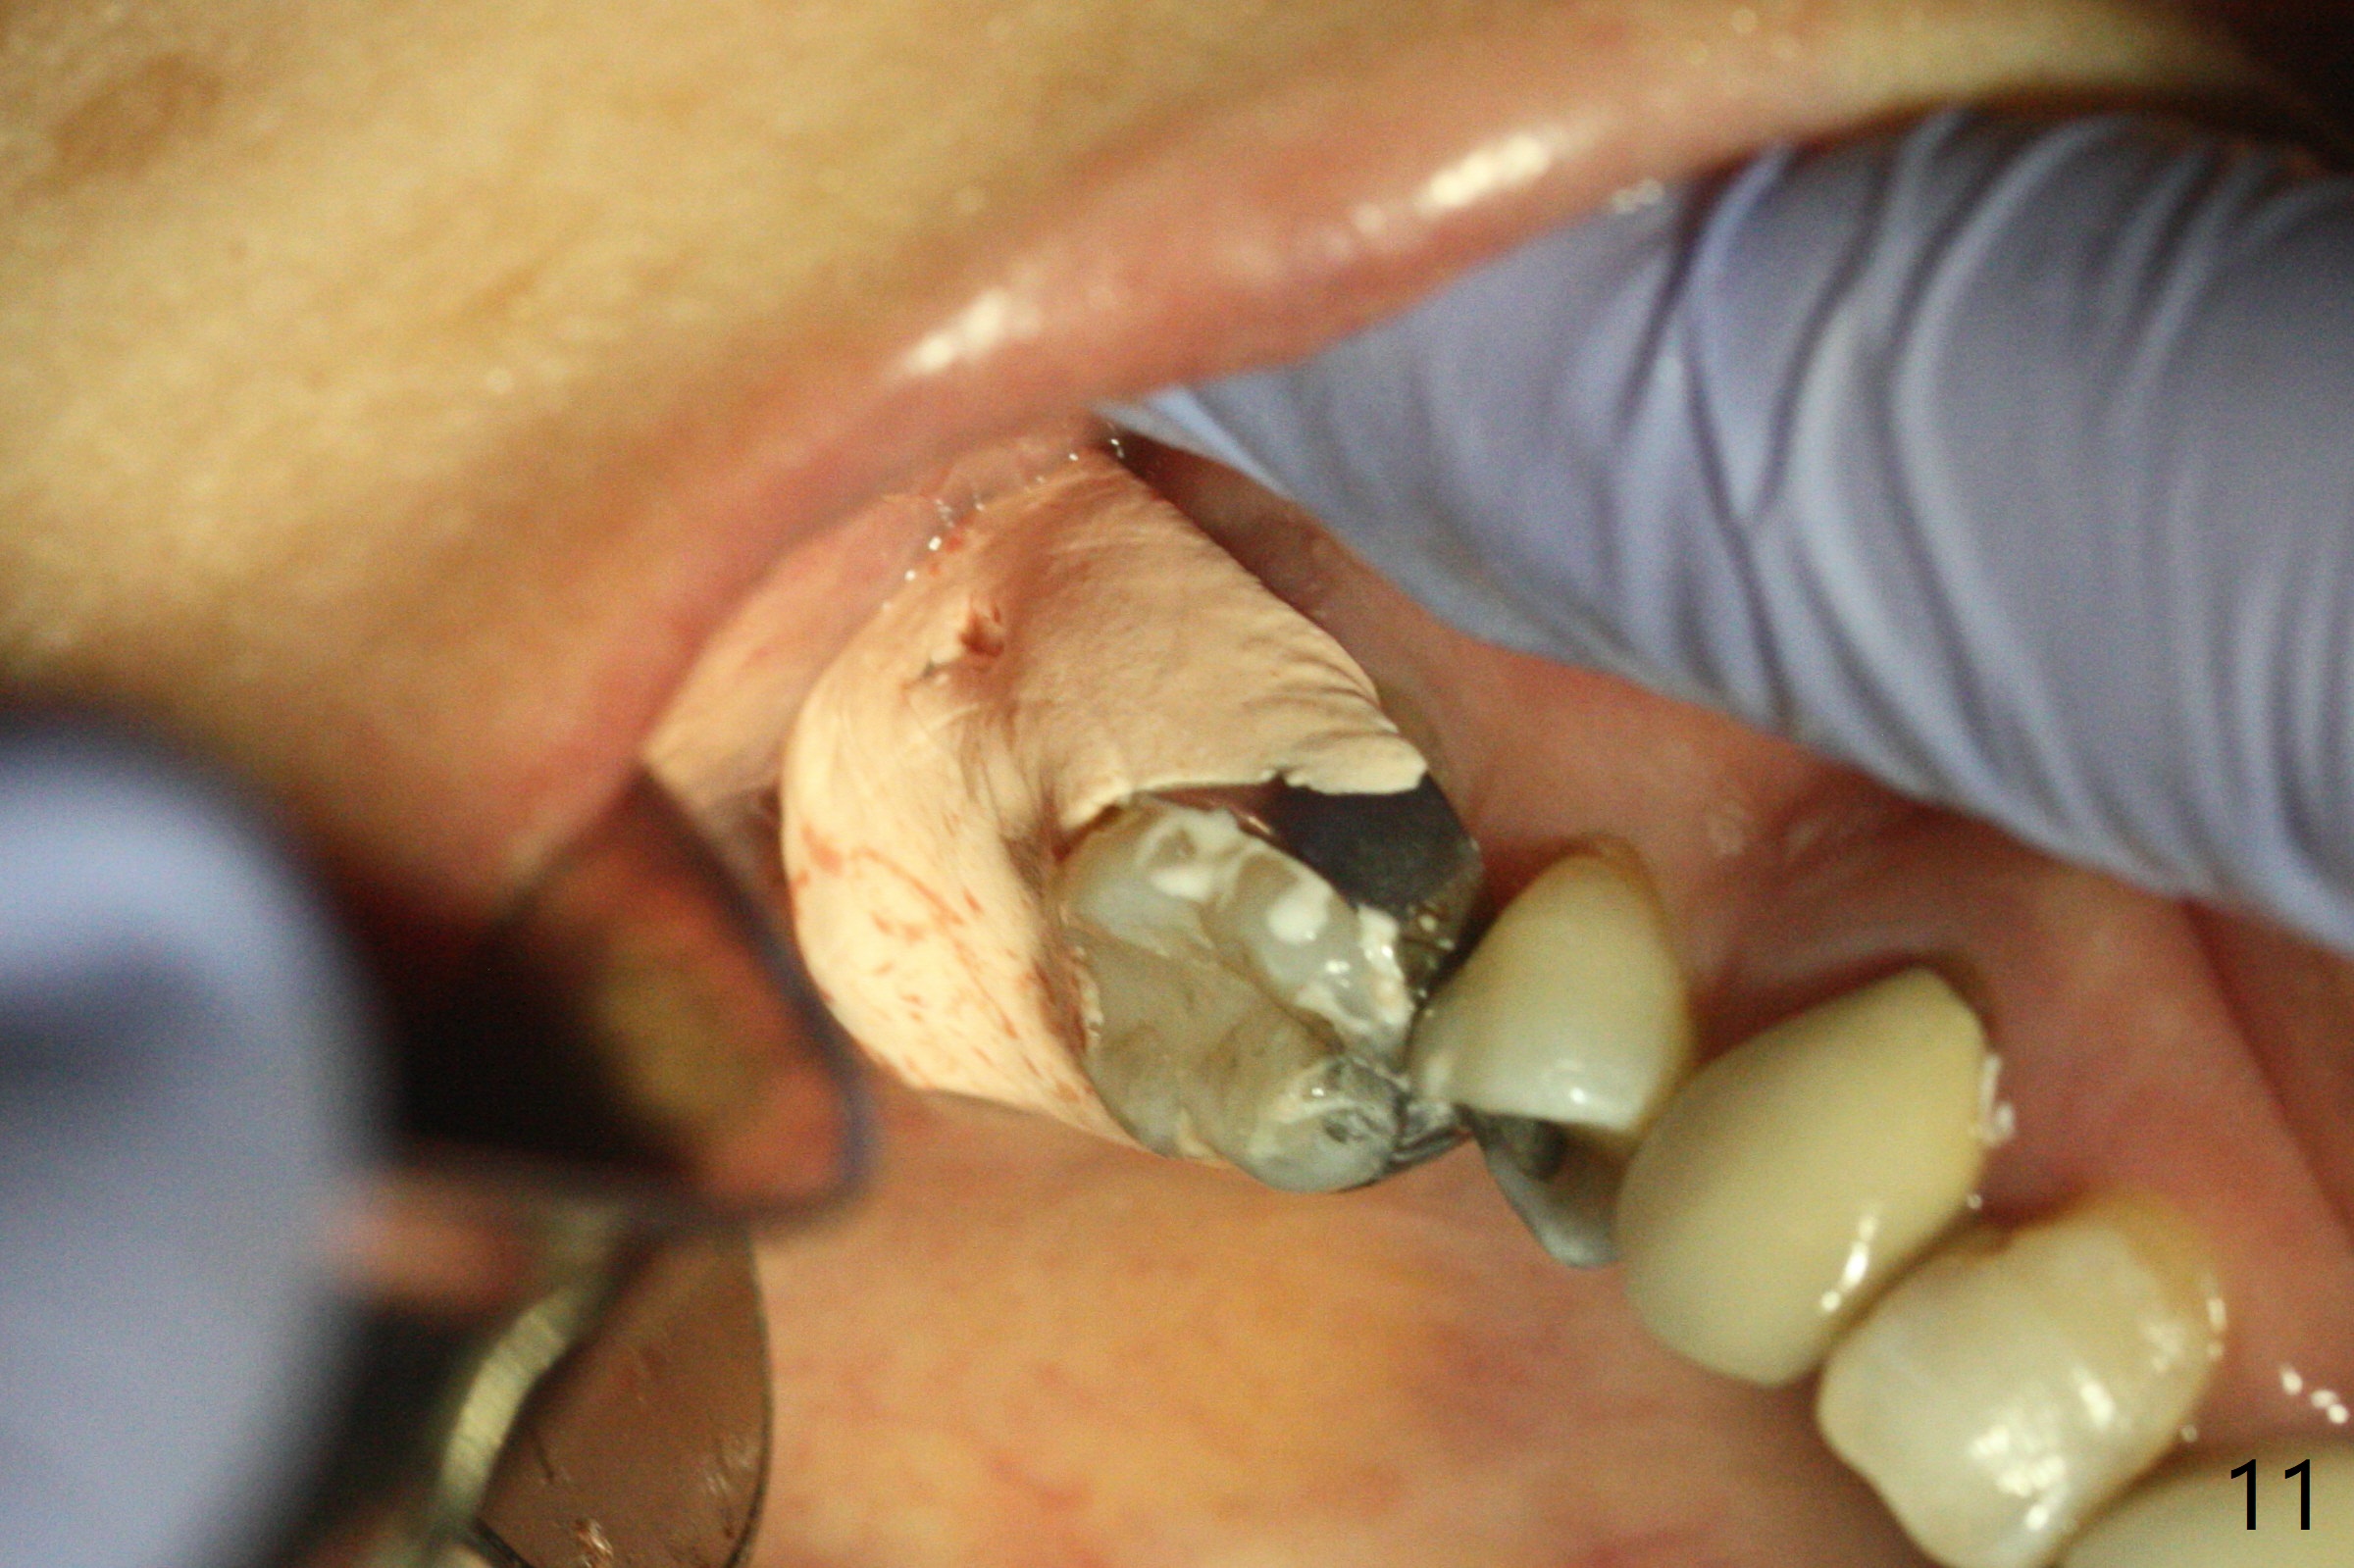

第二磨牙位点保留后,牙周敷料容易脱落,尤其上颌,本文介绍一种方法增加固位。右上七严重牙髓牙周综合征,拔出后使用刮匙除去骨面肉芽组织,颊侧骨板缺失,附着在颊侧粘骨膜上的肉芽组织使用一种叫Stieglitz angled, diamond splinter forceps (德国产,图一,二)撕下来。彻底清除炎性组织必须多次刮治,之间塞入带有灭滴灵(图三:粉剂)和1比50,000肾上腺素局麻药纱布(图四)止血,取出纱布,牙槽窝视野好,继续去除残余的肉芽组织。牙槽窝底部穿孔,用无齿刮匙稍微扩大穿孔后,使用图五下面小的骨粉输送器,将少量骨粉(粘性)送到穿孔处,推入上颌窦(图七:S),之后使用大的骨粉输送器(图五上面),把大量骨粉送到牙槽窝,使用图六上面大的,长的充填器,压实骨粉(图七),骨粉表面放置PRF膜和不可吸收膜(图八),在第一磨牙时安置粘固一个间隙维持器(图九,十),最后铺上牙周敷料(图十一),检查咬合空间,没有干扰。There are sign and symptom of sinusitis 1 week postop; large amount of bone graft retains in the socket by the periodontal dressing and spacer (Fig.12). The sinus membrane (Fig.7 immediate postop) thickens 1 week postop (Fig.13). Augmentin and Medrol Dose Pak are prescribed. 上颌窦炎一周后消失,腭侧牙周敷料丢失,伤口好像正常愈合(图十四)。术后三周牙周敷料由于大量水枪冲洗脱落(图十五)。因为病人需要离城两个月,间隙保持器撤除(图十六),不可吸收膜腭侧稍微外翻 (<),可能有利于术后五周自行脱落。No Deviation SP 下一个病例 位点保留后Xin 导板与张口度 第一磨牙即种 Wei, DDS, PhD, MS 1st edition 09/17/2020, last revision 04/30/2021